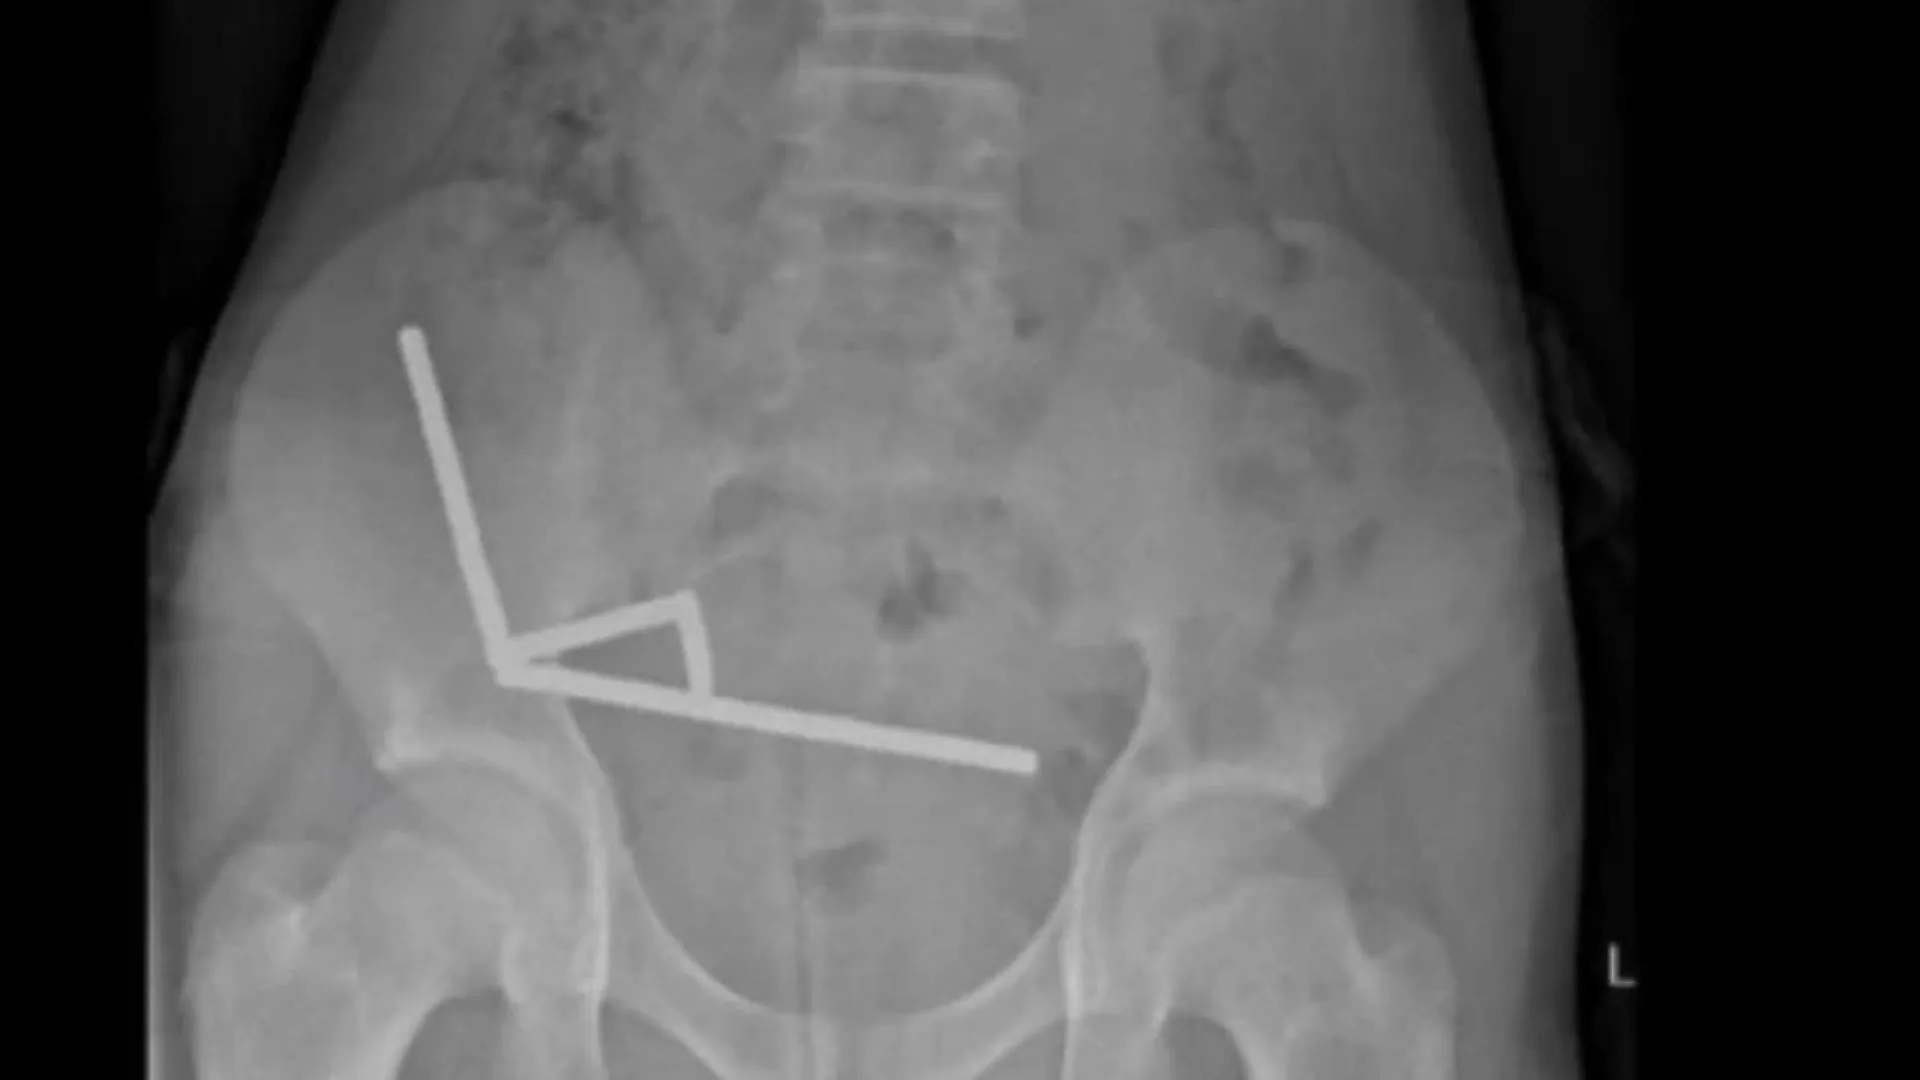

Um garoto de apenas 13 anos perdeu parte do intestino após ingerir 100 ímãs. O caso aconteceu na Nova Zelândia.

Segundo a publicação no jornal do país New Zealand Medical Journal, o garoto teria ingerido entre 80 e 100 ímãs, uma semana antes.

De acordo com o menino, ele mesmo teria comprado os ímãs pela internet, de um site internacional. Os materiais ingeridos eram compostos por neodímio – extremamente magnético – e mediam cerca de cinco por dois milímetros.

Os exames feitos antes da cirurgia mostravam correntes de ímãs em partes do intestino, ligadas pela força magnética. Tal ligação resultou em um necrose por conta da pressão, e quase houve uma perfuração intestinal.

Na operação foram encontradas quatro áreas necrosadas, e parte do intestino do menino teve de ser retirado.